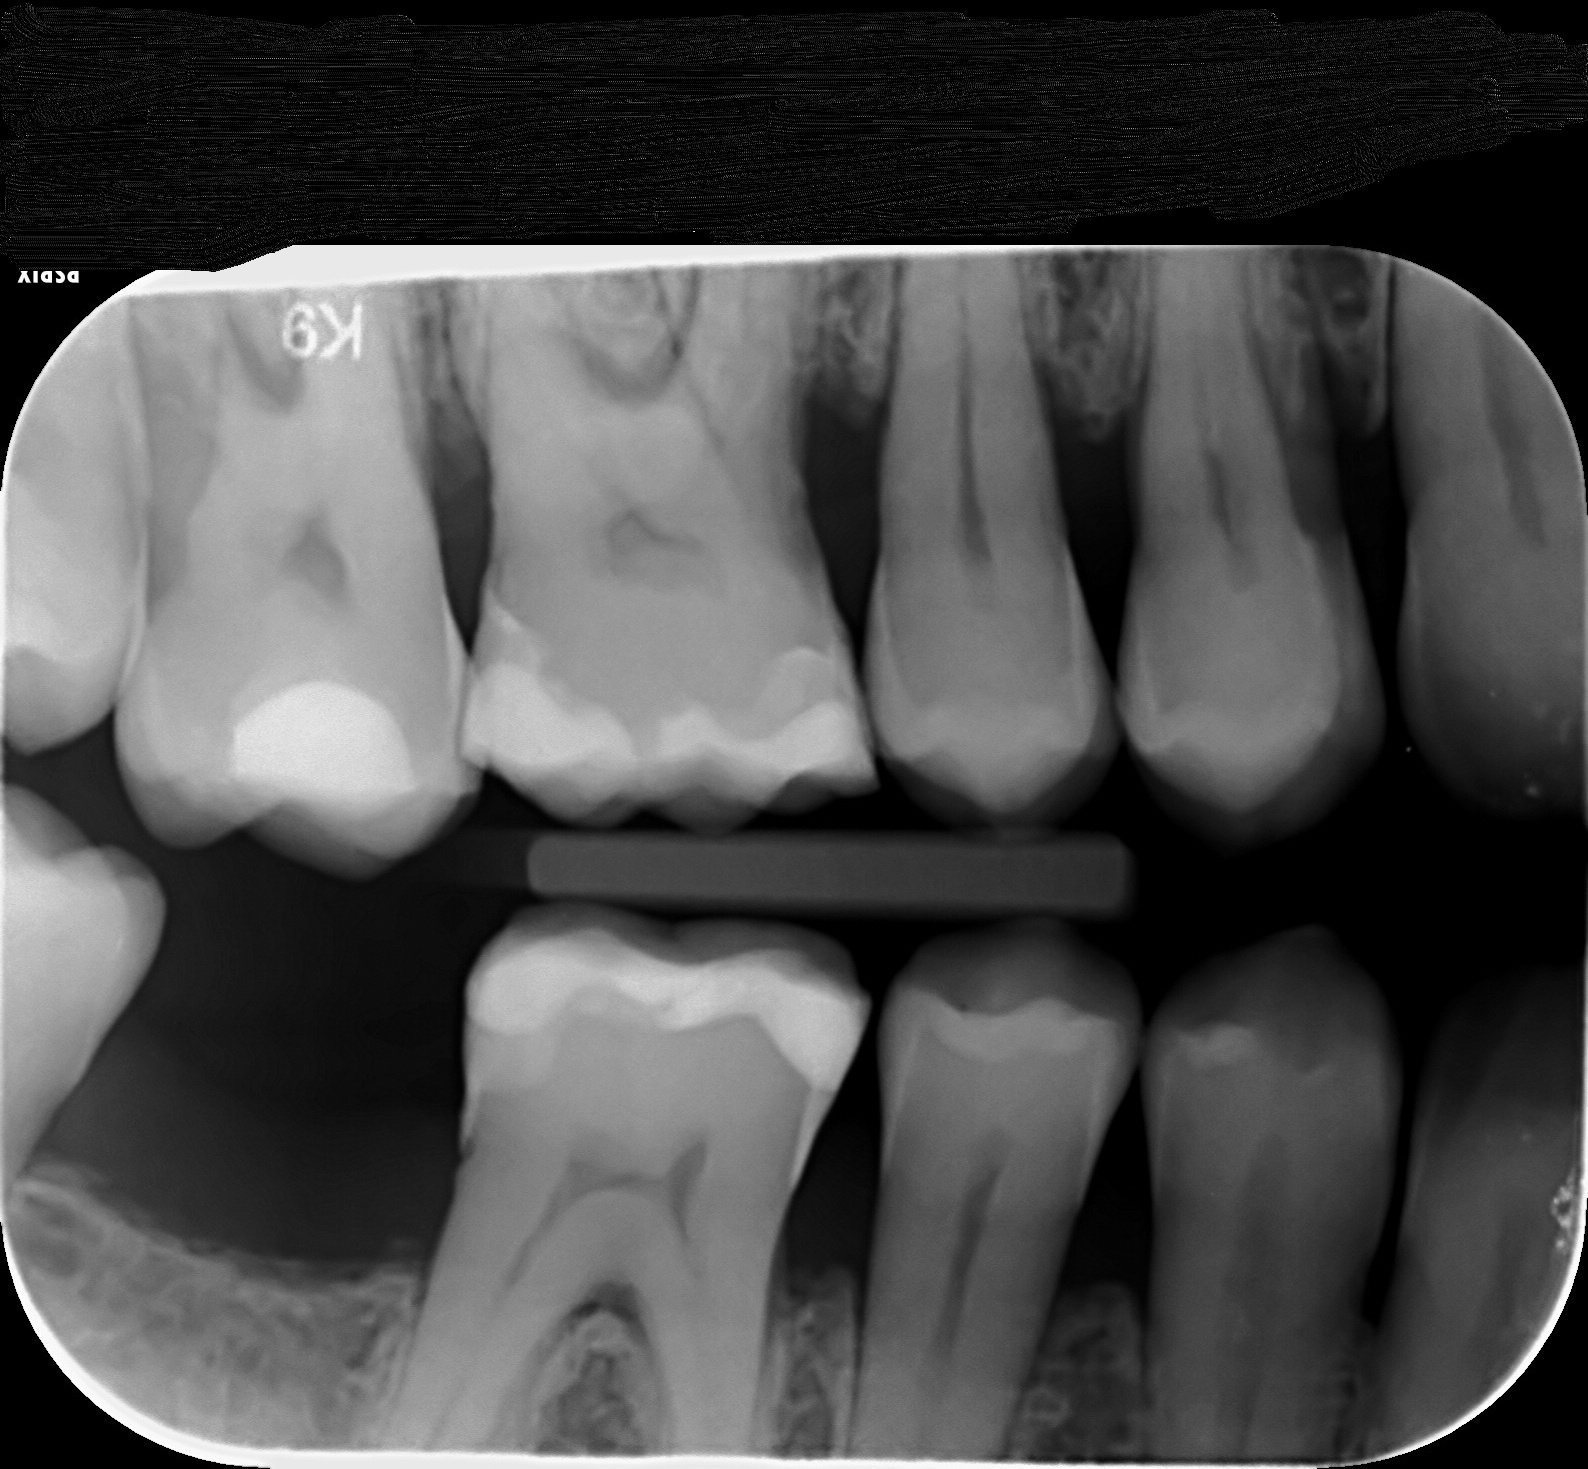

Ik heb de röntgenfoto op gevraagd. Ik vraag me nog steeds af of ik in de 1.8 een gaatje heb. Het gaat hier om de verstands kies rechts boven. Ik zal de röntgen foto hierbij plaatsen. En ook in de 1.7 zie ik een plekje op mijn gebit zitten. Kunt u mijn zeggen aan de hand van de röntgenfoto of er een gaatje in deze kiezen zitten?

Op de 18 zie ik dus geen gaatje, maar een x-foto is niet altijd duidelijk. Het kan zijn dat het aanslag is maar daar voelen wij met een sonde (haakje). De 17 zou mogelijk een overlapping zijn...dat lijkt dan als een "gaatje". Dus sonderen voor meer zekerheid. Als wij toch aan het sonderen zijn zou ik de achterkant v d 16 (hier ook de voorkant) en 46 ook sonderen. Waar ik v schrik is het verlies aan ophanging v d kiezen. Rookt u of heeft u gerookt?. Hoe lang is dit al aan de gang en welk aandacht wordt daaraan besteed?.